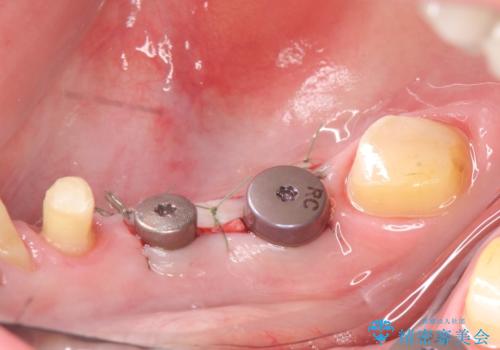

その後右下5、6番目にはインプラントを埋入し、右下3、4、5、6、7番の歯の補綴をオールセラミッククラウンによって行いました。

カスタムアバットについて

カスタムアバットメントは患者様それぞれの歯茎に合わせて製作されたオーダーメイドのアバットメントです。

既製のアバットメントに比べ適合がよく、高い清掃性を誇ります。